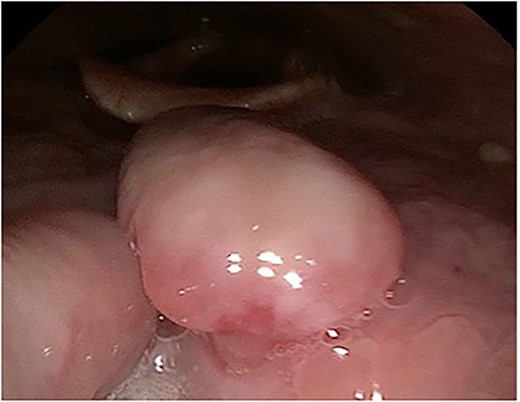

A 63-year-old male with a medical history of hypertension and progressive dyspnoea on exertion, underwent a computed tomography (CT) angiogram for the workup of a pulmonary embolism. There was an incidental finding of a 12-cm left renal neoplasm (Fig. 1), extensive metastatic nodal abdominal disease and bilateral metastatic pulmonary disease (T3 N2 M1). He was discussed at the Urology multidisciplinary team meeting (MDT) and commenced on Sunitnib, given the dissemination of disease. Repeat imaging showed a significant reduction in size of the pulmonary metastasis. Following which, he underwent a cryo-reductive nephrectomy that confirmed a clear cell RCC 102 mm, Grade 3. Development of a tongue lesion after a year warranted Otorhinolaryngology input. Clinical assessment with flexible nasendoscopy depicted a 0.5 cm by 0.5 cm pedunculated lesion on the midline of the tongue (Fig. 2). A biopsy under local anaesthetic confirmed a clear cell RCC (Fig. 3) that was positive for AE1/AE3, Vimentin (Fig. 4) and EMA. Further CT imaging, 1 month after the biopsy confirmed left hilar nodule progression from 2.3 to 3 cm. The medical oncology MDT recommended commencing Nivolumab. Following recurrent bleeding from the tongue, radiation to the area was determined to be the best treatment modality. The patient is still clinically well and tolerating oral intake with no significant large bleeds to date. Regular medical oncology, radiation oncology, urology and Otorhinolaryngology follow-up is ongoing, however, the prognosis is poor with such disseminated disease and the primary focus is on minimising morbidity.

Flexible nasendoscopy image of the pedunculated RCC on the dorsum of the tongue.